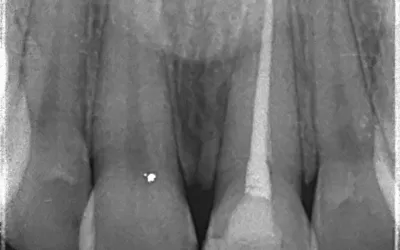

بارداری به دلیل تغییرات هورمونی میتواند سلامت دهان و دندان را تحت تأثیر قرار دهد. التهاب لثه، پوسیدگیهای پیشرفته و حتی عفونت دندانی در این دوران شایعتر است. در شرایطی مثل نیاز به عصبکشی دندان یا حتی کشیدن دندان، گرفتن عکس دندان برای تعیین عمق پوسیدگی یا بررسی وضعیت ریشه ضروری است. اگر این عفونتها درمان نشوند، میتوانند برای سلامت مادر و جنین خطرناکتر از خود عکسبرداری باشند.

اشعهای که در رادیوگرافی دندان استفاده میشود بسیار کم است و به طور مستقیم به جنین نمیرسد. استفاده از دستگاههای دیجیتال امروزی، میزان اشعه را به حداقل میرساند. همچنین در کلینیکهایی مثل کلینیک دندانپزشکی زاگرس، از پیشبند سربی مخصوص برای محافظت از شکم و تیروئید استفاده میشود تا هیچ نگرانی برای مادر وجود نداشته باشد. در نتیجه، اگر نیاز به درمان فوری باشد، عکسبرداری دندان بیخطر محسوب میشود.

بر اساس مطالعات، میزان اشعه رادیوگرافی دندان بسیار کمتر از آستانهای است که میتواند به جنین آسیب برساند. به همین دلیل، اگر همه موارد احتیاطی رعایت شود، عکسبرداری دندان در بارداری خطری ندارد. در واقع، عفونتهای درماننشده دندانی، تهدید جدیتری برای سلامت جنین نسبت به اشعه ایکس محسوب میشوند.